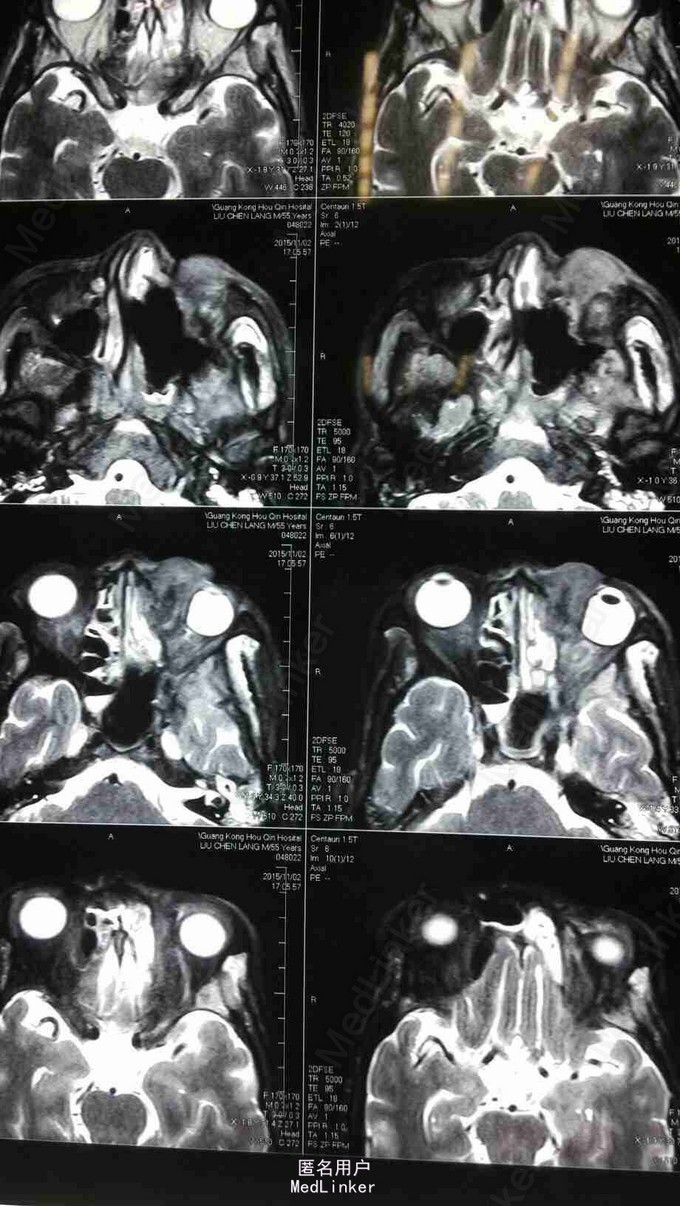

查体:患者神清,消瘦,发音不清,全身浅表淋巴结未见肿大,左眼上睑内侧可见肿物,大小约1*1cm,皮肤红肿,无破溃,质硬,伴压痛,不活动,眼睑闭合不全,睫毛方向正常,眼部可见少量脓性分泌物。 MRI:左侧上颌窦术后改变,左上颌窦顶壁及左眼眶内下方异常信号,考虑肿瘤复发,累及左眶内眦部,前组部分筛窦,内下方肌间隙及上下眼睑内侧份。